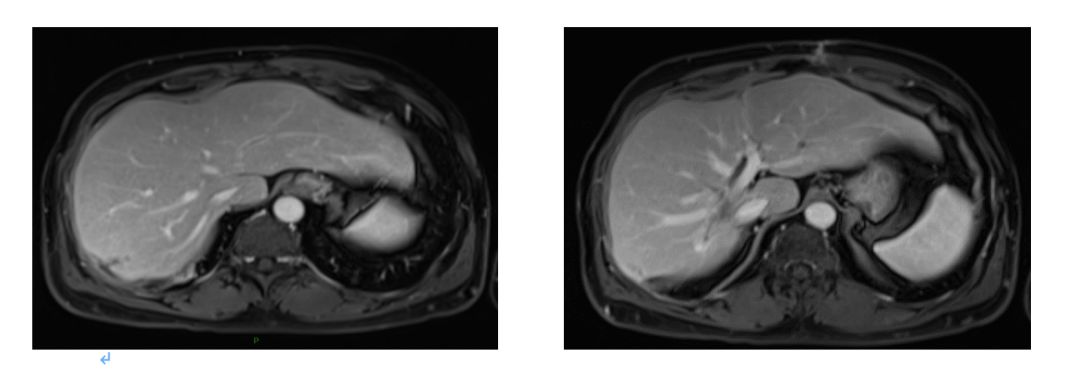

2015.6.16 行肝脏病灶手术+射频治疗,术中B超探查:6个病灶;

见肝脏表面见灰白色转移灶3枚,直径约0.5cm;

肝右后叶近肝门区可扪及质硬肿块约3cm,位于门静脉与腔静脉之间;

肝右叶近膈顶处及肝左叶肿块各一枚,大小约1cm;

射频消融三处:肝S8、S1及S2转移灶。

术后: 4周期西妥昔单抗+FOLFIRI化疗;

2015.9 肝S8段病灶区域DT45Gy/15F放疗。

2016.4.28肝脏MRI:治疗后改变。